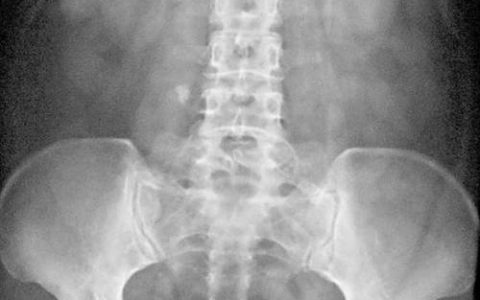

A 24-year-old man presents for his annual physical and is noted to have a nontender right testicular nodule. After an initial ultrasound, he is sent for CT imaging of his abdomen and pelvis, which shows enlarged para-aortic lymph nodes that are greater on the right side. What testicular pathology does this patient most likely have?

一名 24 岁的男性参加了他的年度体检,发现右侧睾丸结节无压痛。 初步超声检查后,他被送去接受腹部和骨盆的 CT 成像,显示右侧较大的腹主动脉旁淋巴结肿大。 该患者最可能患有哪种睾丸病变?

睾丸癌最常见于 15 至 35 岁的男性,精原细胞瘤是最常见的类型,约占睾丸癌的 40%。 睾丸癌的淋巴扩散常见于主动脉旁淋巴结链。